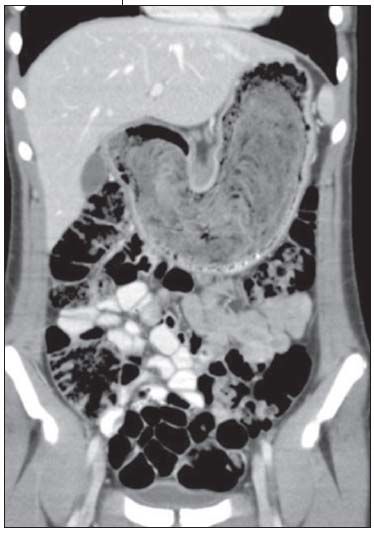

Figure 2 – Coronal CT scan shows the large, heterogeneous, laminated mass filling the gastric lumen from the fundus to the antrum.

Mononucleosis from possible exposure was the presumptive diagnosis; however, results of a rapid heterophile antibody test were negative. Liver function panel, complete blood cell count, erythrocyte sedimentation rate, and serum uric acid levels were all within the normal range. An abdominal ultrasonogram revealed an epigastric mass and normal spleen. Abdominal CT scan findings were indicative of a large gastric bezoar (Figures 1 and 2), which was promptly removed by laparotomy, without complication.